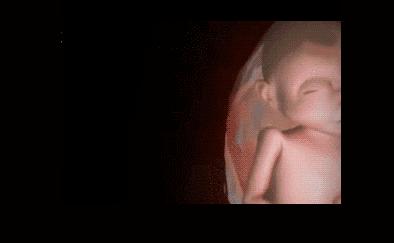

其实小家伙很小的时候就已经开始“闹腾”了:妥妥的一个运动健将!

小碎步向前缩,撅着小屁股用力一蹬,身体向后滑去——“母胎版蛙泳”动作很标准嘛!

不行,刚才的动作不够标准,再来一次!

不过,力气好像还是太小了,算了,休息休息再说~